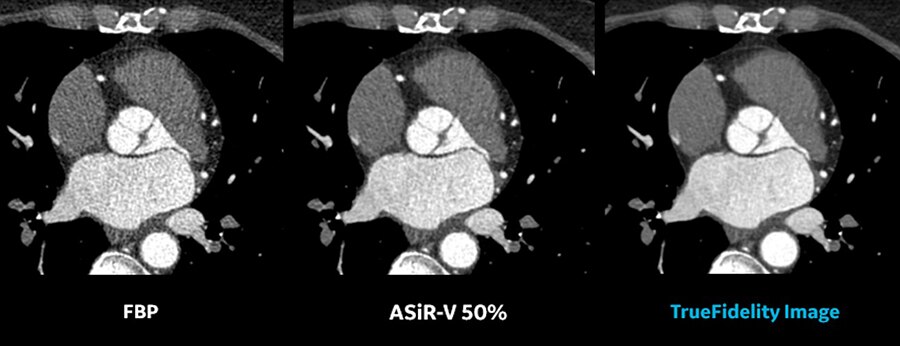

Image Gallery : Reconstruction Technology Comparison

FBP

ASiR-V 50%

Deep Learning Image Reconstruction

1. As demostrated in a clinical evalution consisting of 60 cases and 9 physicians, where each case was reconstructed with both DLIR and ASiR-V and evaluated by 3 of the physicians. In 100% of the reads, DLIR's image sharpness was rated the same as or better than ASiR-V's. In 91% of the reads, DLIR's noise texture was rated better than ASiR-V's. This rating was based on each individual reader's preference.